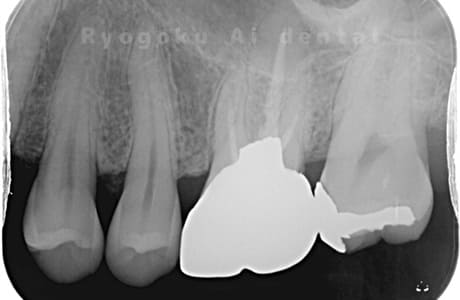

Case07

- 慢性根尖性歯周炎(16・17・15部)

- 治療内容

- マイクロエンド(3歯分)

- 308,000円(3歯分)※被せ物を除く

右上の違和感が取れないとのことで来院された患者さんです。ファイルという器具が歯の根の中で折れていることを説明し、マイクロスコープを使用した根管治療を提案し、治療を行いました。折れたファイルも取り除くことができ、現在の経過は良好です。